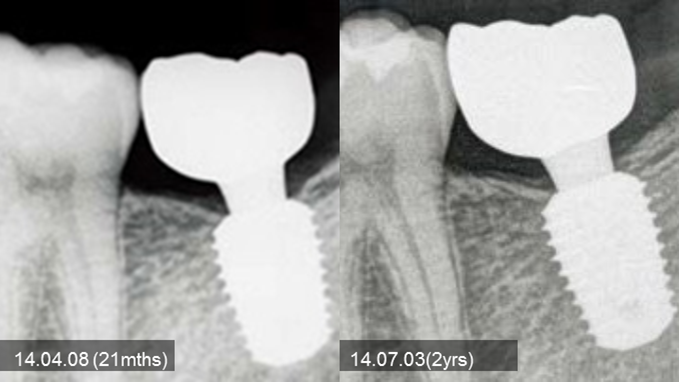

Clinical case: Bone filling into the bottom of deepest thread at 8.0mm AnyRidge fixture

- Courtesy of Dr. Kwang Bum Park -

Keywords

AnyRidge, Knifethread ,extraction socket, ,initial stability ,Allograft, ,osseointegratio ,Dr. Kwang Bum Park, , Mandibular, Single replacement, AnyRidge, Mega-oss,

Products used

Implant system-AnyRidge, Regeneration-Mega-Oss